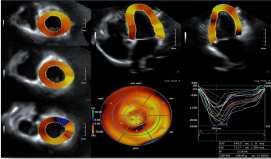

10. 全面的心脏应用:Aplioi900可为临床提供全方位心脏超声解决方案,支持专业的经胸心脏探头及经食道探头。

1) 二维/三维室壁运动追踪技术 (2D/3D Wall Motion Tracking)

2) 心脏容积成像